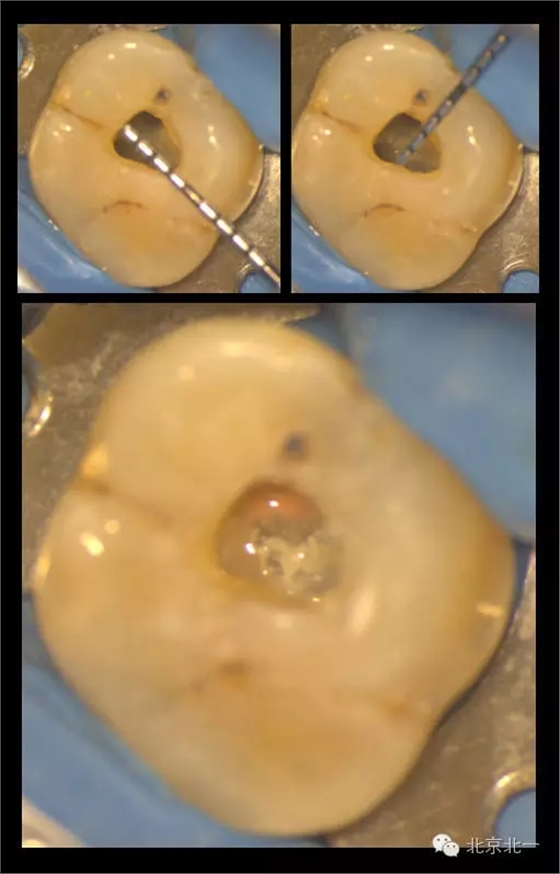

在我們看來,微創(chuàng)的入路設(shè)計是需要條件限制的。首要條件就是在入路開放后醫(yī)師能明確牙齒內(nèi)根管的分布與走行。醫(yī)師或者在術(shù)前通過CBCT明確根管解剖行程,或者能夠從開髓入口處檢視到髓底的全部區(qū)域以防遺漏根管。

下圖是我們研究生小苑的課題,在顯微CT的輔助下,借助牙面標(biāo)記點進行髓腔入路的設(shè)計:根據(jù)CT數(shù)據(jù)建立的根管模型,將每個根管的延長線投影至牙冠表面,連接各表面投影點后即為開髓的通道。這樣的開髓入路下,既暴露出了所有根管口,從不同的視角方向下也能看到完整的髓底解剖。